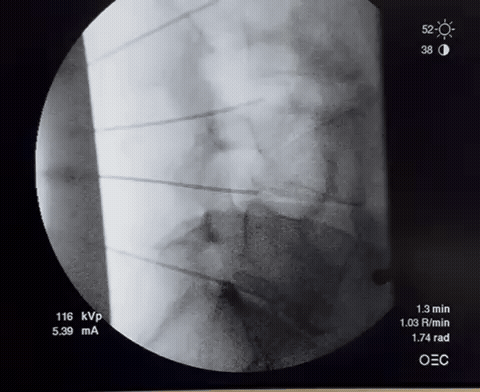

During your annulogram™, we inject X-ray contrast and a trace of antibiotic into each disc's outer annulus fibrosus to reveal tears. Then, The medication is promptly injected to seal the tears and promote tissue growth, healing the discs over time.

During the Discseel® Procedure, lasting about 40 minutes in an outpatient setting, you'll receive mild sedation for comfort. Using x-ray fluoroscopy, your physician will inject contrast mixed with an antibiotic into each disc, pinpointing disc tears. Then, under x-ray guidance, essential components of Fibrin are injected into the tears, sealing damaged discs. Over months, Fibrin promotes tissue growth, aiding in disc healing.